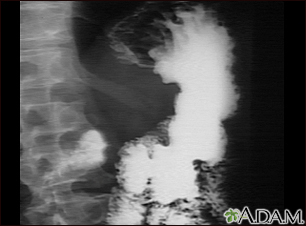

Stomach cancer, x-rayBackStomach cancer, x-rayAn upper GI series in a patient with cancer of the stomach (gastric carcinoma). E-mail FormEmail ResultsName:Email address:Recipients Name:Recipients address:Message: